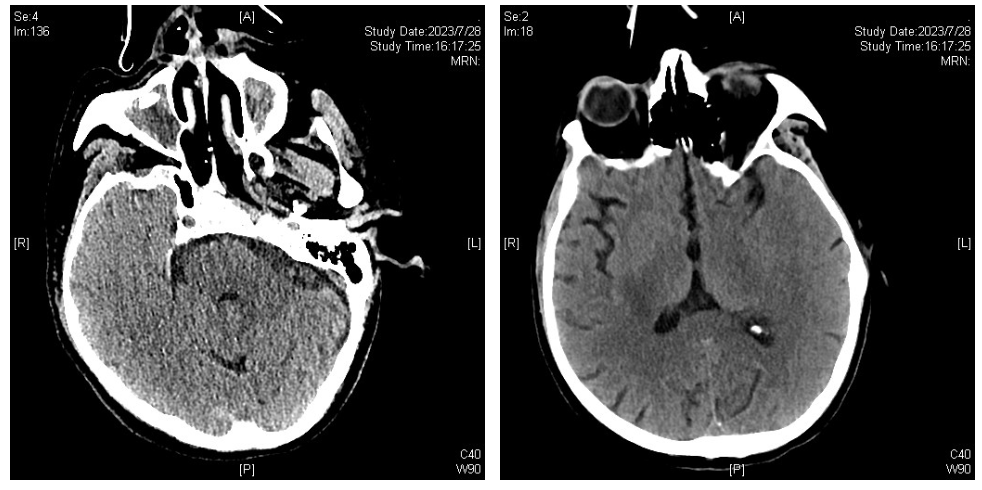

患者于7月10日上午出现口齿不清,但对答切题,无肢体活动障碍等。下午出现嗜睡,左侧肢体活动度较右侧差;伴气促加重。头颅CT:脑实质未见异常密度,双侧上颌窦炎,真菌感染可能。胸部CT:双肺感染较前加重,左上肺舌段、双下肺实变,双侧胸腔少量积液。

图8. 头颅CT(2023-07-10)

疗效评价:患者未再发热。神智清楚、言语欠清楚,左侧肢体肌力进一步下降。呼吸衰竭相对稳定,氧合指数维持在200 mmHg以上。血象无明显恢复,仍是持续粒细胞缺乏、中度贫血、血小板减少(波动在2万~5万)。7月28日复查胸部及头颅CT:双肺病变加重并出现双侧大量胸腔积液;右侧侧脑室、丘脑旁低密度,双侧上颌窦炎,真菌感染可能。再次行气管镜并送检灌洗液mNGs。并双侧胸腔置管引流,提示渗出性胸腔积液,留取胸水送检mNGS。灌洗液及胸水mNGs仍提示嗜肺军团菌。患者出现的肢体功能障碍,明确为脑梗塞导致,因患者持续存在血小板低下及凝血功能异常,未予抗凝及抗血小板治疗。

图11. 头颅CT(2023-07-28)

8月14日,复查影像学检查(依拉环素治疗14天),胸部CT:双肺感染较前吸收好转,双侧胸腔积液较前减少;头颅CT:右侧大脑半球低密度影范围较前增大,考虑脑梗塞并右侧颞叶出血可能,上颌窦炎,真菌感染可能。

图16. 头颅CT(2023-08-14)